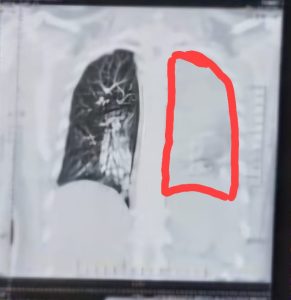

In next morning another X ray done in erect posture that shows hugely distended loop of gut in her left mediastenum that had pushed the left lung upwards.

To support the X-ray, a CT chest done . CT report was as same as X ray. In some section of the CT scan lung tissue was totally absent and in some section lungs was confined only in apical region.

Finally it was diagnosed as a diaphramatic hernia. Intestinal loops entered into the thoracic cavity and trapped. So her abdomen became distended, lung tissue compressed to the upper zone the left side.